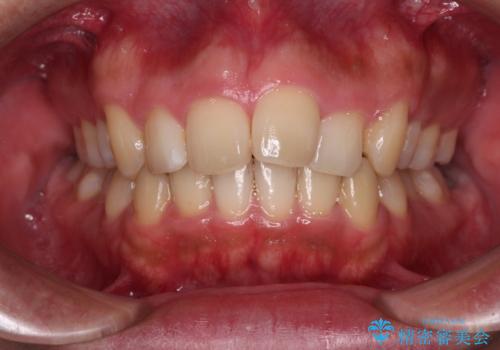

- 学生時代に抜歯矯正した歯列が後戻りしてきたとのことで来院された患者様です。

舌の突出癖が原因で上顎前歯が前方に移動したと考えられたため、舌のトレーニングを徹底して行っていただきながら、後戻りを解消していくこととしました。